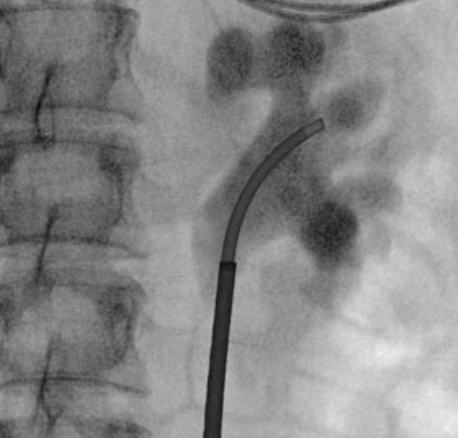

@roger_sur @DrMaheshDesai4 @PurplePMan @BEkidneystone @GeorgeHaleblian @UCSD_Urology @DukeUrology @BWHUrology How big is the lumen? Inner/outer? Looking for investors?